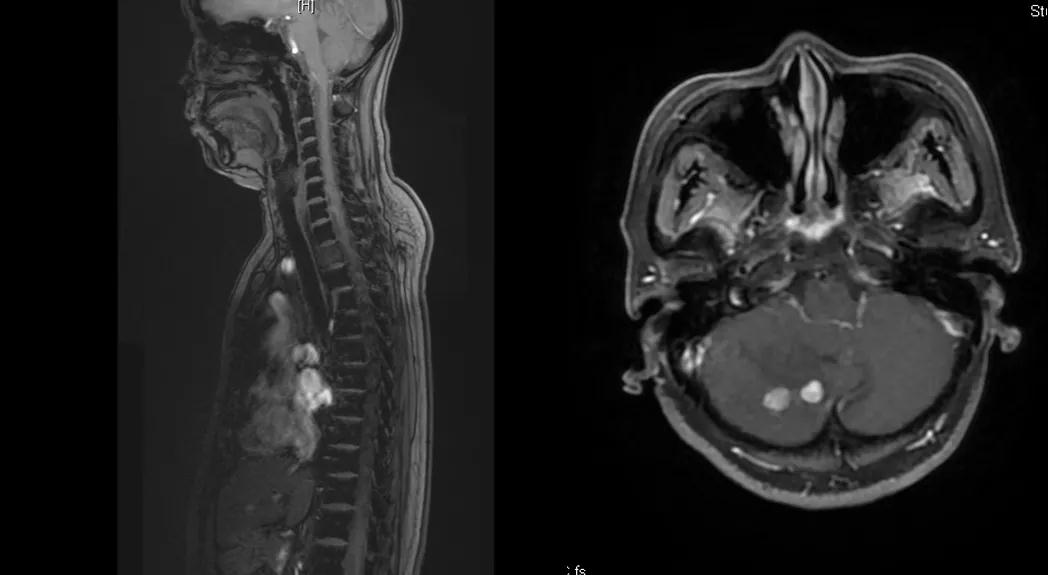

曲妥珠单抗辅助治疗结束6个月后,患者出现左侧胸部疼痛,ECT检查提示:左侧第4、5肋骨及T2胸椎转移;MR提示:T2椎体转移,肝S6段异常强化灶,考虑转移瘤可能性大;脑转移(图1)。

图1

给予T-DM1治疗。治疗6个月后复查MR显示脑、肝、骨转移瘤均较前明显缩小,达到部分缓解(PR)(图2)。目前PFS已达10+个月。

图2